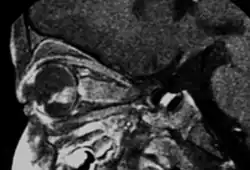

Aspect of trilateral retinoblastoma on MRI -